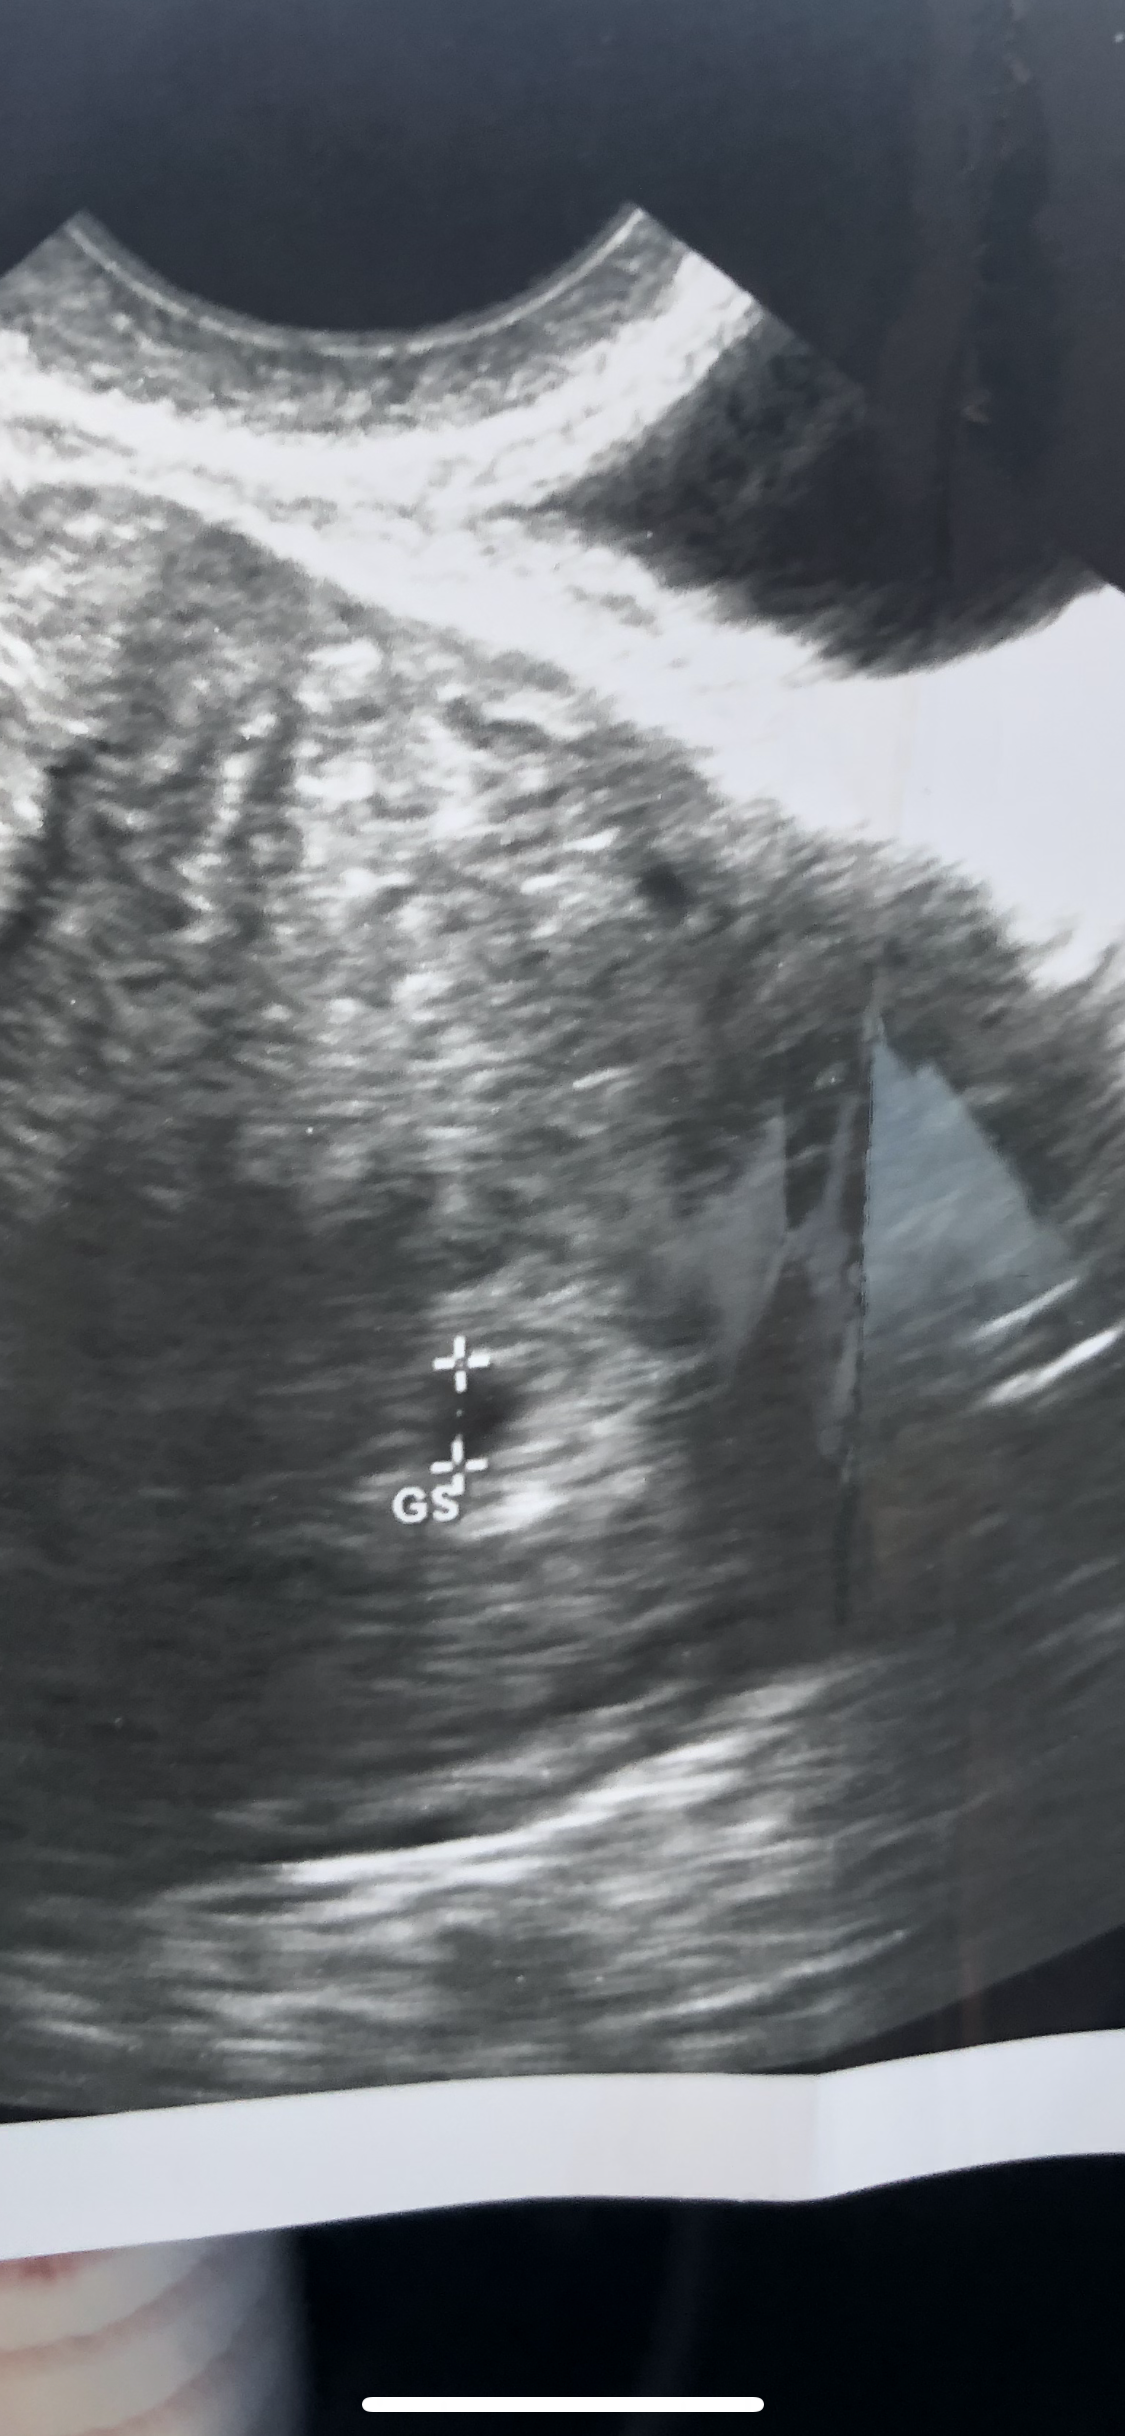

Is it possible that this is 2 sacs?

Anyone? Edit* I understand *most of you* are not medical professionals. I am simply asking if you “see” 2 sacs. Maybe someone has had an ultrasound and had something similar happen. I am not asking “am I pregnant”, “is this twins”, “what gender do you think this sac is”. Don’t worry, I am deleting my account.

• OP- no need to be so sensitive. No one was rude. I see two black dots but I’m also thinking that if the tech thought it was twins, both dots would have been measured.